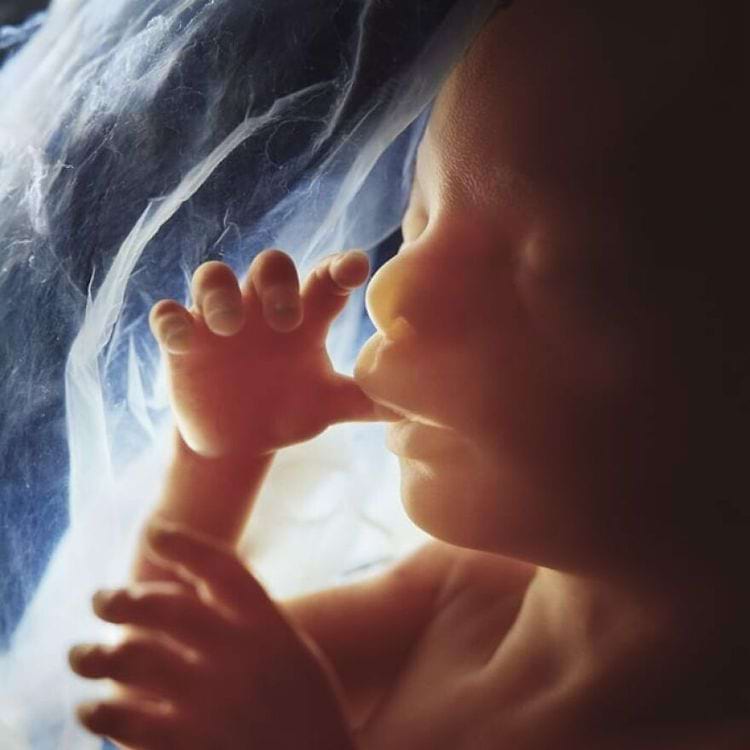

20 недель, 1974 год